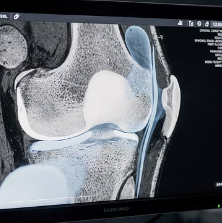

3. 반월상연골 손상

무릎 관절 안에 있는 연골판이 손상되면 염증 반응이 나타납니다.

무릎이 잠기는 느낌이나 특정 각도에서 통증이 심해지는 경우가 많습니다.

젊은 층에서도 운동 중 발생할 수 있습니다.

4. 인대 손상

십자인대나 측부인대 손상 후 무릎에 물이 차는 경우도 흔합니다.

외상 이후 갑자기 무릎이 붓고 통증이 심해지는 것이 특징입니다.

보행이 어려워질 정도로 불편할 수 있습니다.